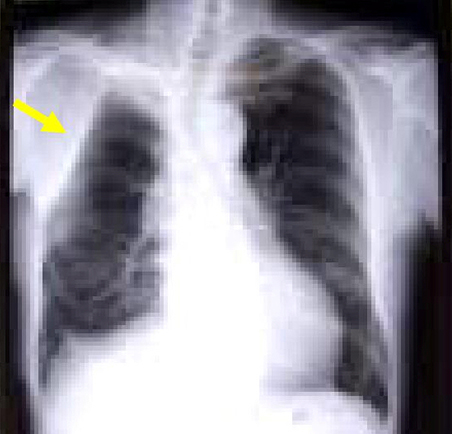

(1)胸壁浸潤肺癌の術前・術後の胸部単純X線および術中写真です。手術は右肺上葉切除術+胸壁合併切除(右第2~6肋骨切除)+縦隔リンパ節郭清を施行しました(下図)。

術後 胸部XP

(2)右肺癌+巨大胸壁転移の症例に対して右肺上葉切除+縦隔リンパ節郭清ならびに胸壁転移切除・腹直筋による胸壁再建術(下図)。